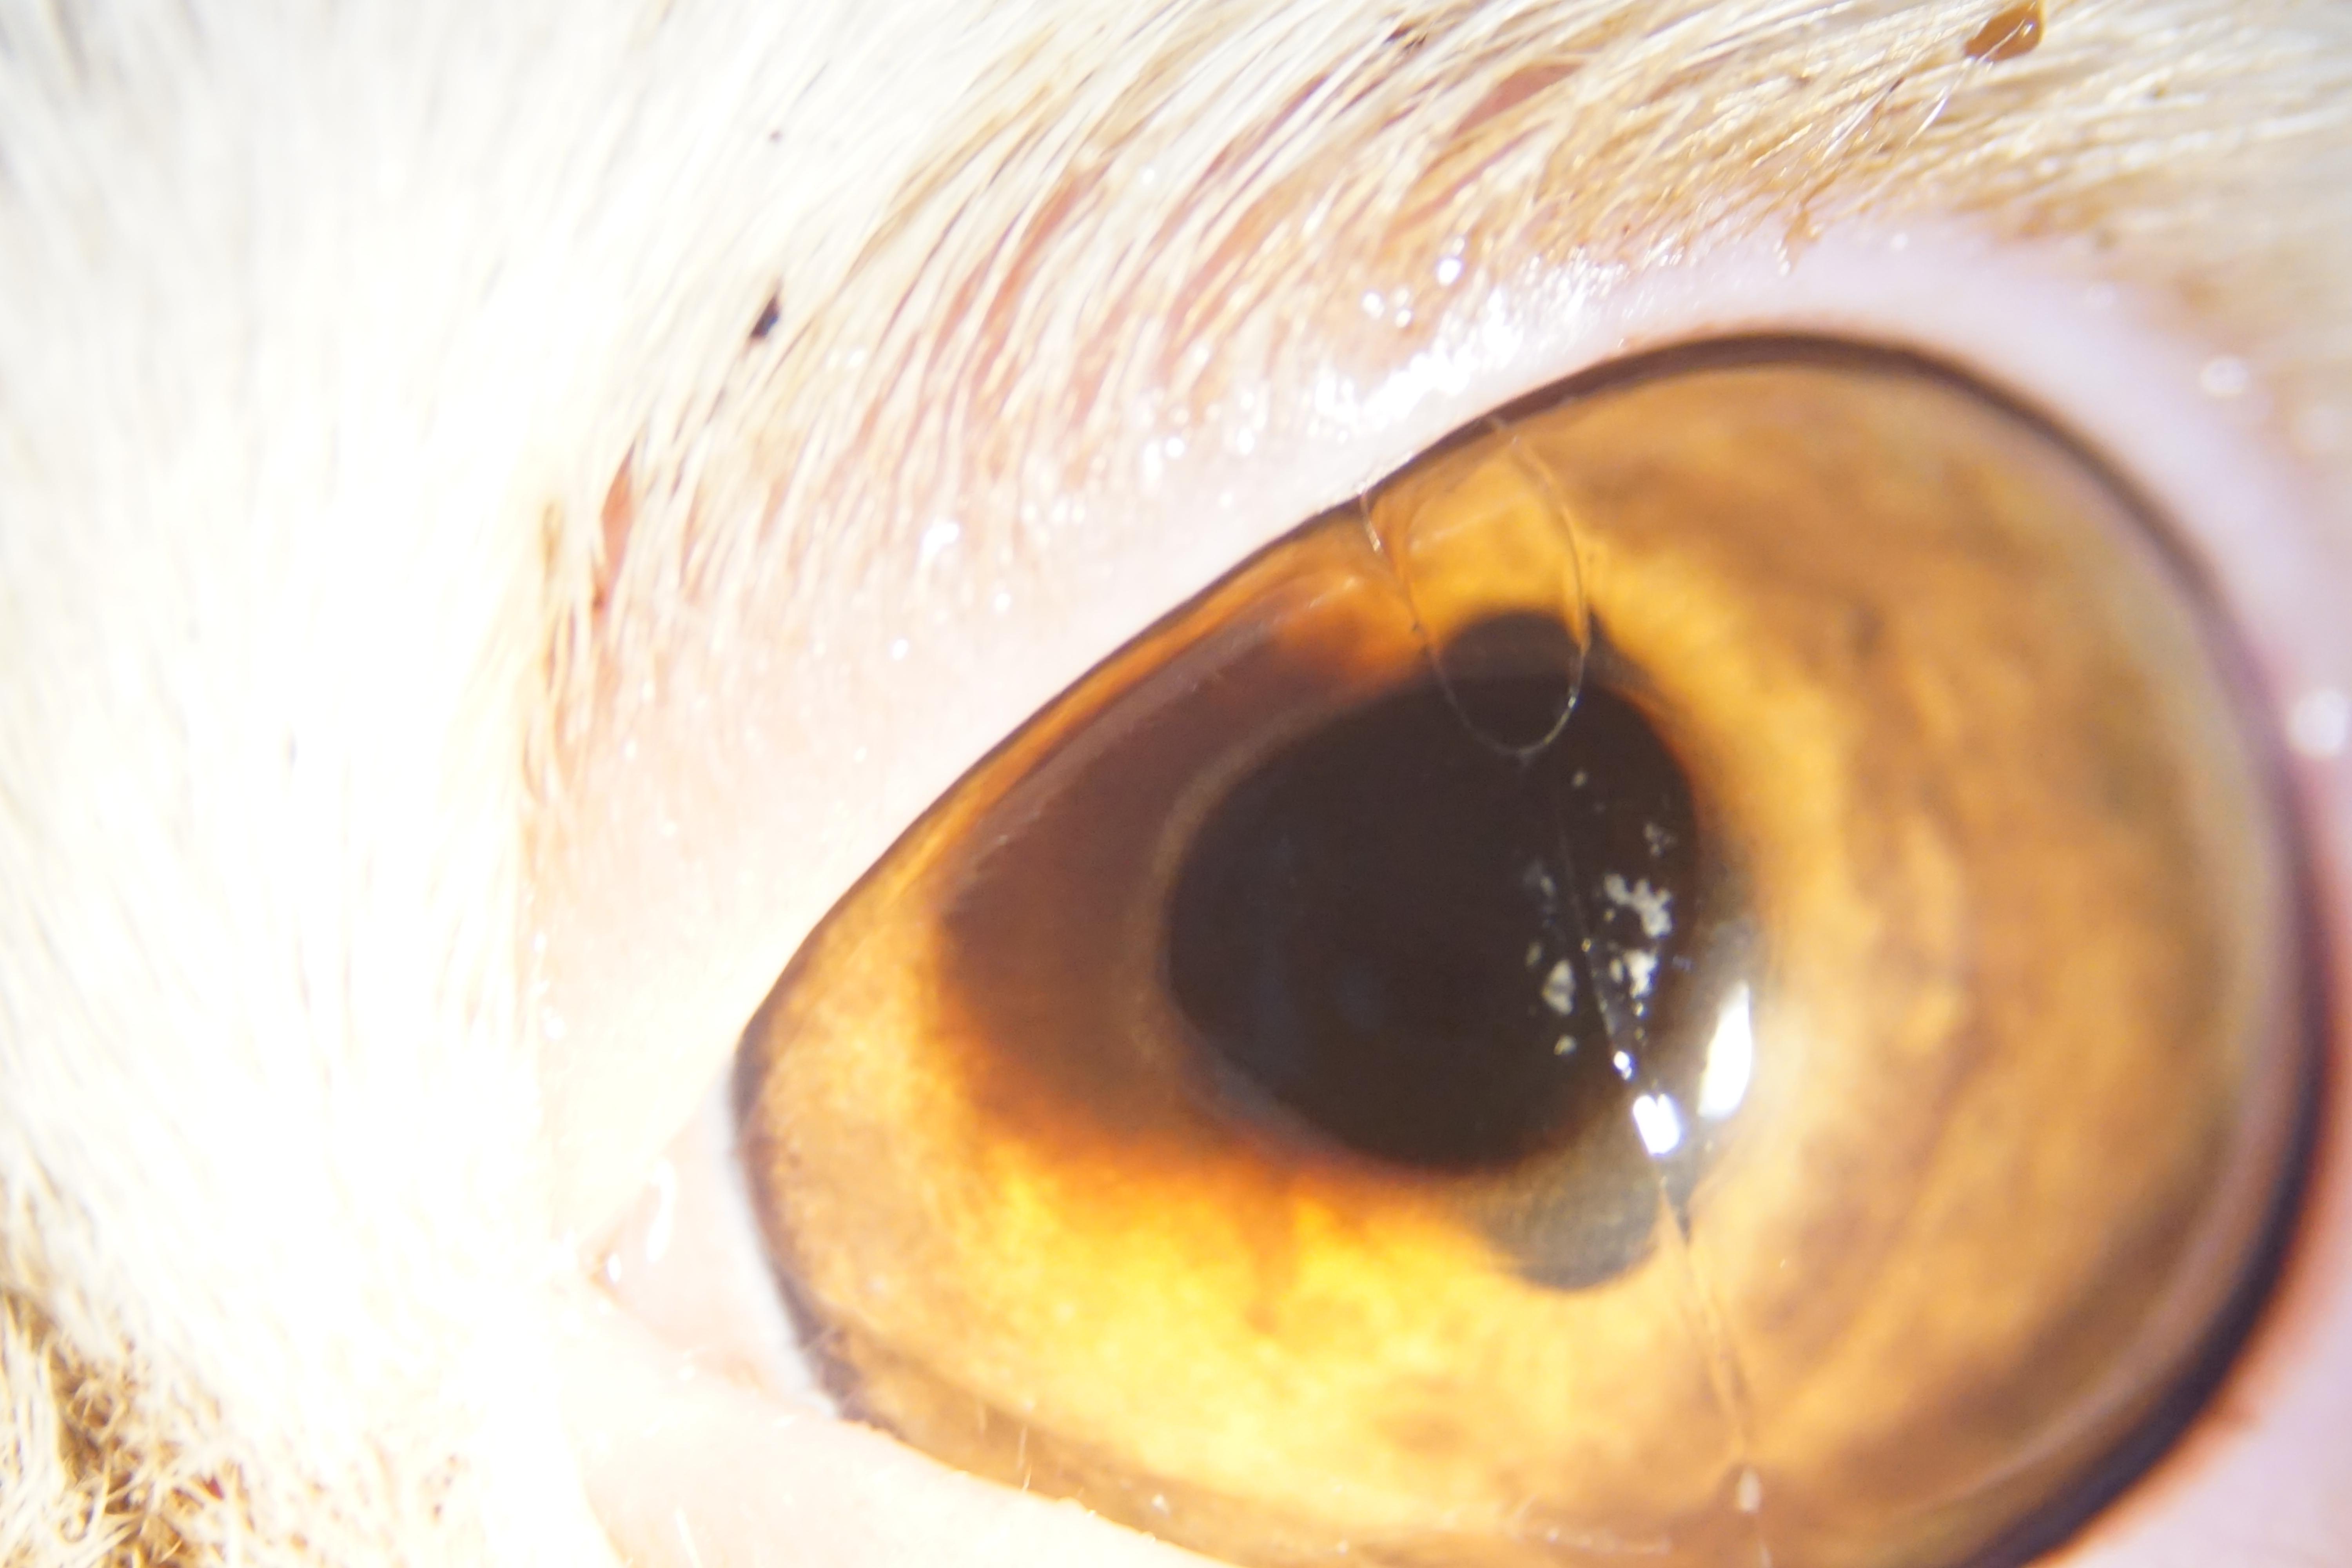

异国短毛猫,雄性,两岁,未去势,角膜腐骨患病时间6个月,长期点眼透明质酸钠,更昔洛韦,头孢甲肟。

2.临床检查

2.1、眼科理学检查:

2.2、眼科器械检查

2.3、裂隙灯:

3.诊断结果

根据以上综合诊断过程,确诊病例为角膜腐骨。